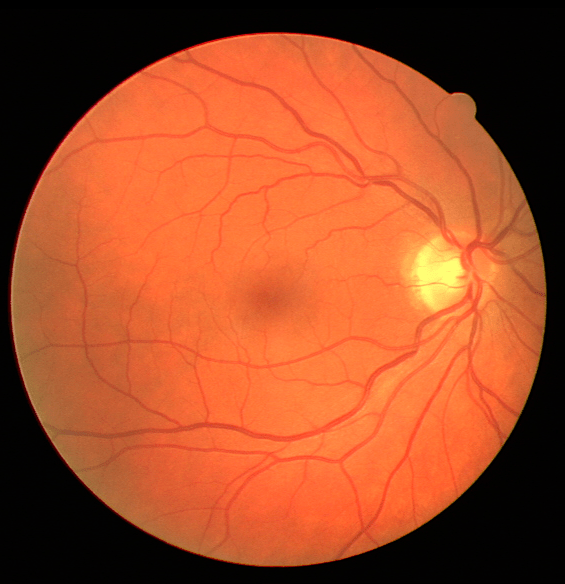

III The RAVIR Dataset

Recently there has been a substantial increase in the utilization of single wavelength confocal imaging that only captures reflected light passing through a pinhole, which will allow capturing high quality, high contrast fundus images. The images in our RAVIR dataset were captured using infrared (815nm) Scanning Laser Ophthalmoscopy (SLO), which in addition to having higher quality and contrast, is more convenient for the patient and is less affected by opacities in optical media and pupil size. This imaging modality is also commonly used in ophthalmology clinics. The RAVIR dataset consists of 46 IR retinal images from the UCLA Stein Eye Institute imaging database, divided into train and test sets of 26 and 20 images, respectively. We used 4 images from the 26 test images as our validation set. The images were captured using a Heidelberg Spectralis camera with a FOV. They are sized at pixels and compressed in the Portable Network Graphics (PNG) format. Each pixel in the images has a reference length of 12.5 microns. Table I compares our RAVIR dataset against other retinal vessel segmentation datasets.

VI-A Retinal Artery and Vein Segmentation

As reported in Table IV, we compared the SegRAVIR model against competing deep learning-based segmentation approaches on the RAVIR dataset. Evidently, SegRAVIR outperforms these methods as judged by all metrics for artery and vein classes with a healthy margin. In terms of Dice score, SegRAVIR outperforms CE-NET, IterNet and AG-Net by , and for artery segmentation and by , and for vein segmentation, respectively. Fig. 4 presents a qualitative comparison of the semantic segmentation outputs of SegRAVIR, CE-Net, and U-Net. Specifically, SegRAVIR yields more accurate vessel topology (i.e., thickness and orientation) segmentation with higher pixel-wise classification accuracy.

Table V presents quantitative performance benchmarks of SegRAVIR and other competing approaches for retinal artery and vein classification on the RITE dataset [11]. SegRAVIR outperforms previous state-of-the-art approaches in terms of accuracy, sensitivity, and specificity. Fig. 5 provides a qualitative comparison between segmentation outputs of SegRAVIR and the method of Hemelings et al. [40] on the RITE test set.

Using the final pretrained student SegRAVIR model in our knowledge distillation framework described in Section IV-D, we fine-tuned and tested the network on three publicly available datasets of color images, DRIVE [10], STARE [9], and CHASE_DB1 [12]. Fig. 7 shows example of SegRAVIR segmentation outputs on DRIVE and CHASE_DB1 datasets. Table VII presents a quantitative comparison between the segmentation performance of our SegRAVIR model and state-of-the-art models: R2U-Net [25], DU-Net [26], and IterNet [34]. By all evaluation metrics, SegRAVIR has achieved new state-of-the-art results on the DRIVE, STARE [9], and CHASE_DB1 datasets.